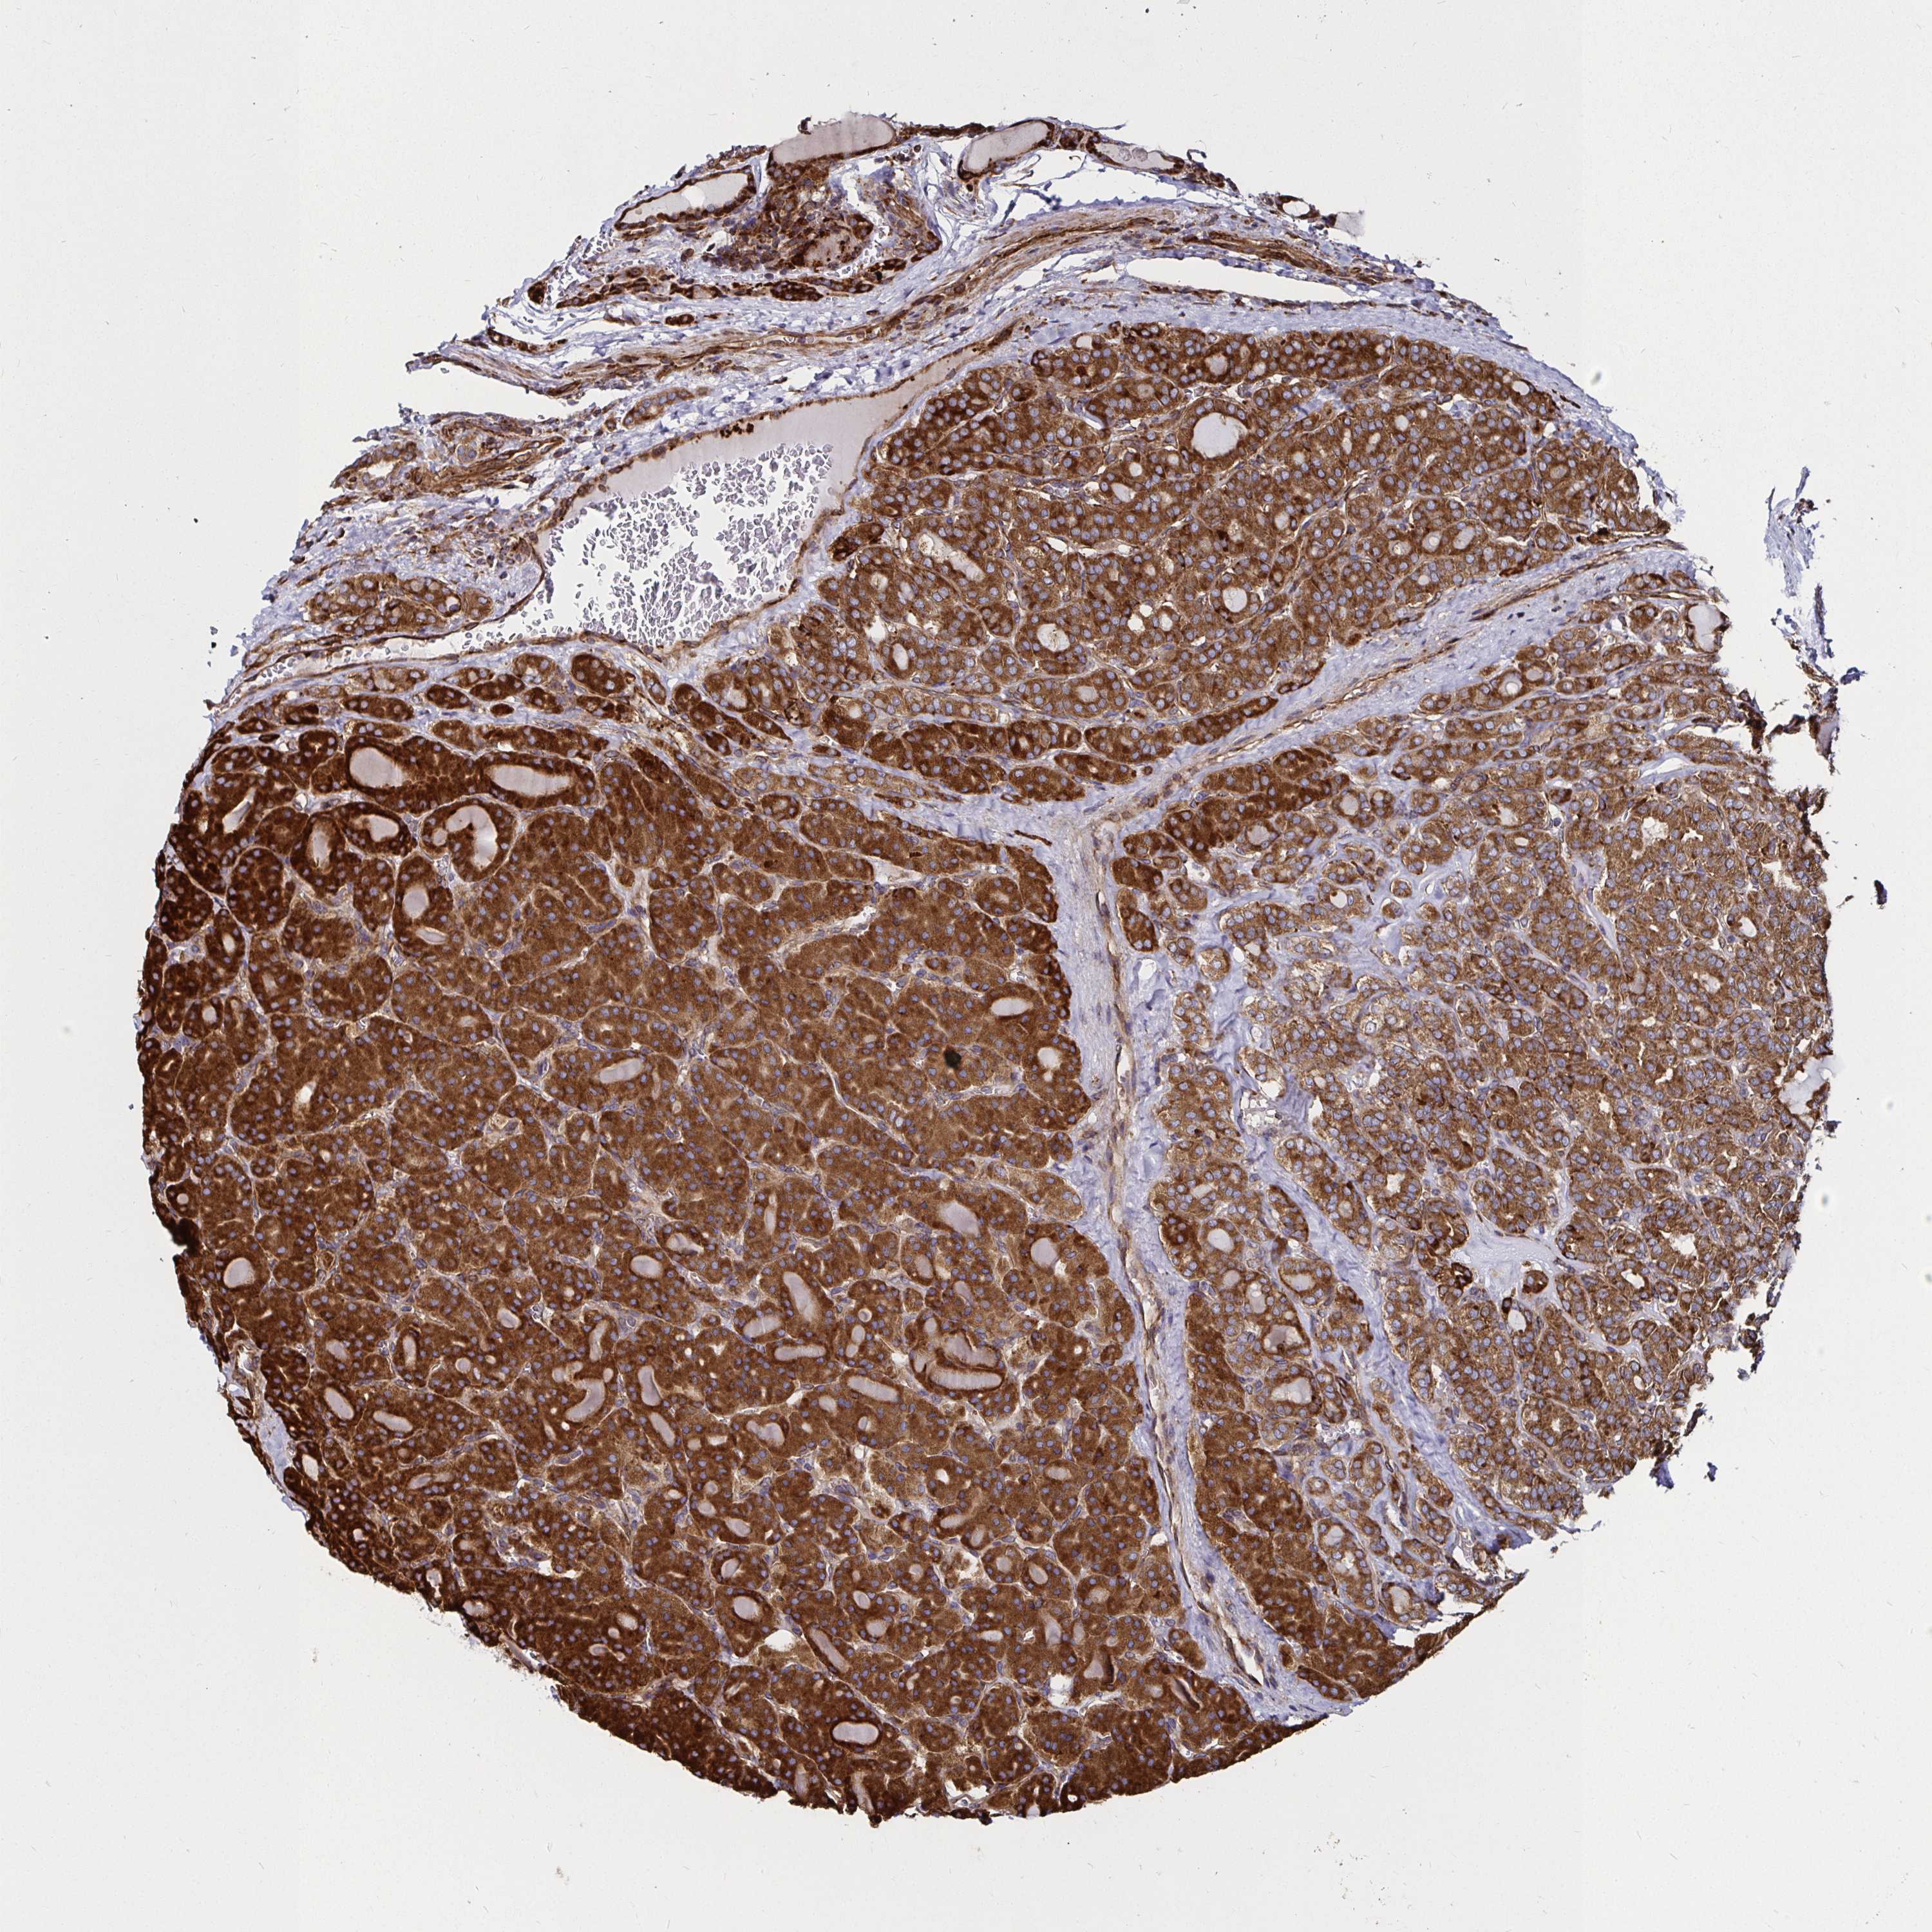

THYROID CANCER - Protein expressioni

A mouse-over function shows sample information and annotation data. Click on an image to view it in a full screen mode. Samples can be filtered based on level of antibody staining by selecting one or several of the following categories: high, medium, low and not detected. The assay and annotation is described here.

Note that samples used for immunohistochemistry by the Human Protein Atlas do not correspond to samples in the TCGA dataset.

Antibody stainingi

Antibody staining in the annotated cell types in the current human tissue is reported as not detected, low, medium, or high, based on conventional immunohistochemistry profiling in selected tissues. This score is based on the combination of the staining intensity and fraction of stained cells.

Each image is clickable and will lead to virtual microscopy that enables deeper exploration of all samples and also displays staining intensity scores, fraction scores and subcellular localization as well as patient and tissue information for each sample.

Antibody HPA045821

Antibody HPA054352

Antibody CAB012229

Staining

High

Medium

Low

Not detected

Intensity

Strong

Moderate

Weak

Negative

Quantity

>75%

75%-25%

<25%

None

Location

Nuclear

Cytoplasmic/membranous

Cytoplasmic/membranous,nuclear

Papillary adenocarcinoma, NOS

Follicular adenoma carcinoma, NOS